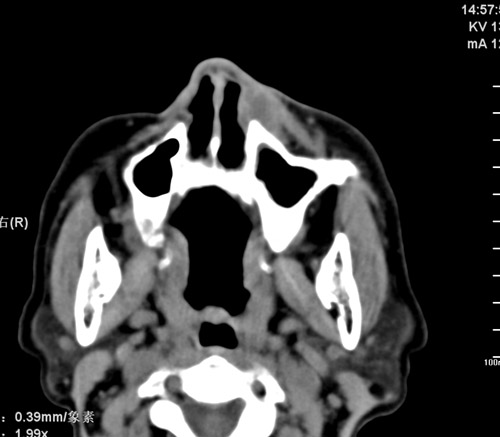

标题: CT17755:女,74 左鼻旁肿胀半年,临床以左上颌窦旁占位行CT [打印本页]

标题: CT17755:女,74 左鼻旁肿胀半年,临床以左上颌窦旁占位行CT

ct考虑鼻前庭囊肿 或鼻翼基底部慢性炎症,左上颌窦少许炎症 请指教

1)考虑左侧鼻前庭囊肿并感染。2)双侧上颌窦炎。

左侧鼻前庭囊肿并感染。双侧上颌窦炎。支持